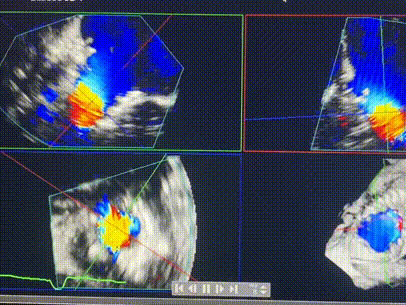

手術(shù)在全麻狀態(tài)下進行。術(shù)者采用經(jīng)右側(cè)頸靜脈入路的方式將輸送器送入患者心臟內(nèi),在TEE及DSA引導(dǎo)下調(diào)整輸送器頭端角度,使得輸送器與三尖瓣瓣環(huán)平面垂直。在輸送器進入右心室后釋放室間隔錨定裝置,而后釋放瓣葉夾持件(2個耳片結(jié)構(gòu))成垂直狀態(tài)。在TEE及DSA確定夾持件固定至三尖瓣葉根部且位于右室側(cè)后釋放人工瓣心房側(cè)盤片。隨后調(diào)整瓣膜同軸性以及室間隔錨定件位置(貼合室間隔),前推藏針管并固定,進而釋放室間隔錨定裝置,并再次確認瓣膜位置、穩(wěn)定性及同軸性,合攏輸送鞘后撤出輸送器,完成LuX-Valve Plus人工三尖瓣瓣膜的植入,僅殘余微量瓣周漏。且經(jīng)手術(shù)中心電生理團隊評估,病人的起搏器和ICD功能沒有受到影響。

術(shù)后超聲顯示僅殘余微量瓣周漏

LuX-Valve Plus經(jīng)血管三尖瓣置換系統(tǒng)此次“出海”圓滿完成,術(shù)后Rodrigo Estévez-Loureiro教授對LuX-Valve Plus經(jīng)血管三尖瓣置換系統(tǒng)的器械性能和治療效果大為稱贊,認為LuX-Valve Plus的手術(shù)體驗非常好。術(shù)后即刻超聲顯示三尖瓣反流幾乎完全消失,血流動力學(xué)改善顯著,患者恢復(fù)快。在面對復(fù)雜解剖結(jié)構(gòu)、超聲影像質(zhì)量不佳、有起搏導(dǎo)線干擾時,Lux-Valve Plus也體現(xiàn)了極強的適應(yīng)性。Thomas Modine教授和Anson Cheung教授也肯定了LuX-Valve Plus術(shù)中操作的便捷性,認為LuX-Valve Plus容錯率高,對術(shù)中影像的依賴較小,后期希望可以更多的應(yīng)用LuX-Valve Plus三尖瓣置換系統(tǒng)于臨床實踐,讓更多的三尖瓣重度反流患者盡早獲益,改善預(yù)后。